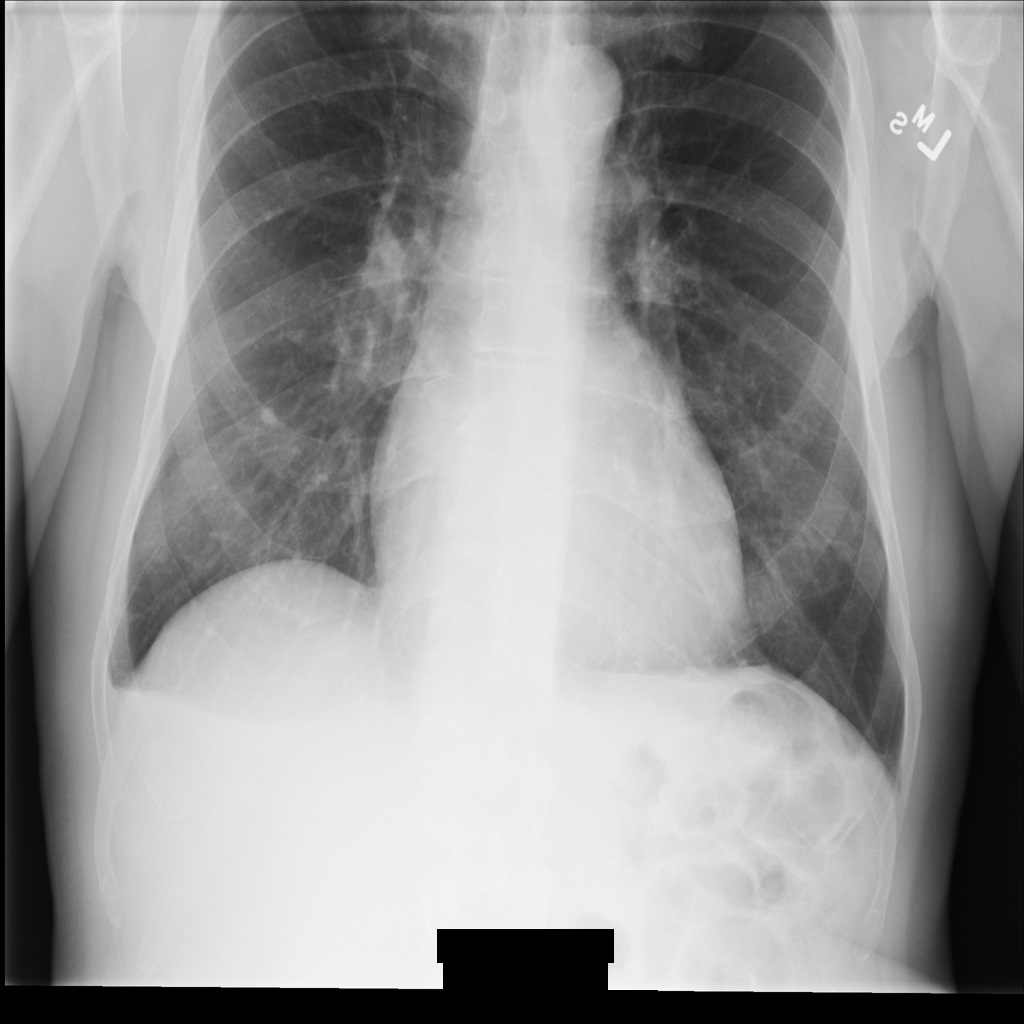

Imagem de amostra

Algumas amostras nesta página contêm uma saída da imagem desidentificada. Cada amostra usa a seguinte imagem original como entrada: É possível comparar a imagem de saída de cada operação de desidentificação com esta imagem original para ver os efeitos da operação: